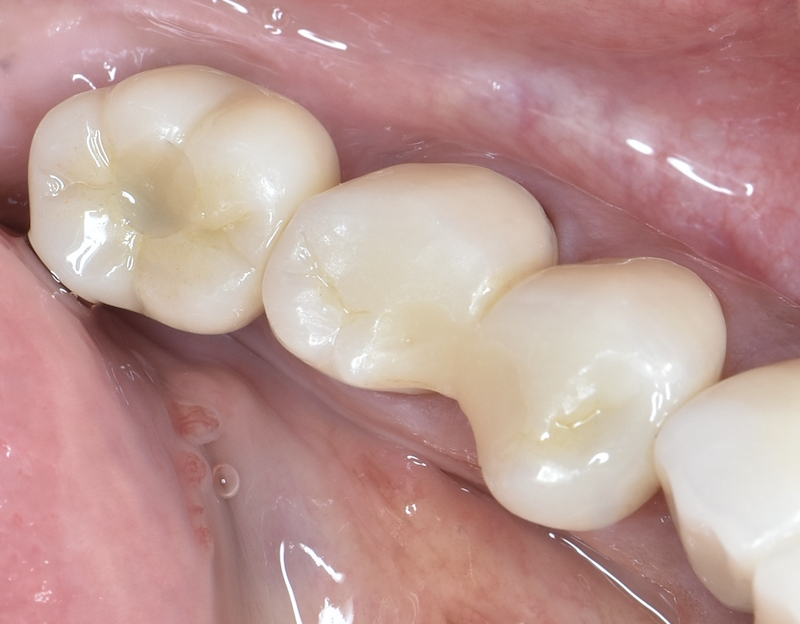

After

根が割れて抜歯が必要になった部分に骨を補う処置

(リッジプリザベーション)を行い、骨が成熟するのを待ってインプラントを埋入しました